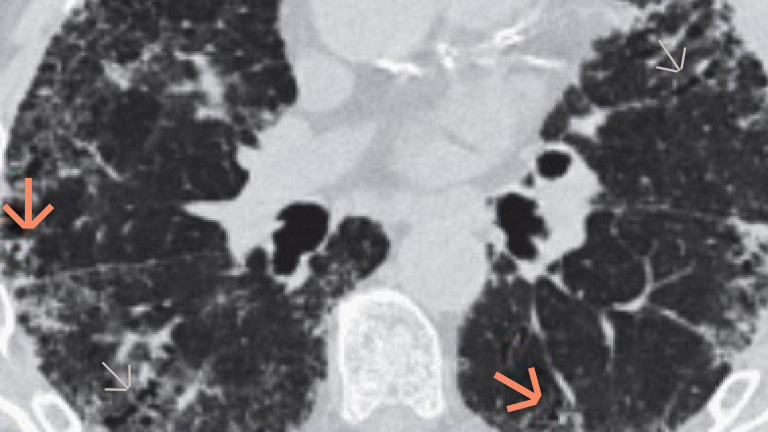

Ten atlas obrazowania może pomóc w diagnostyce ILD, ułatwiając rozpoznawanie kluczowych wskazówek i typowych cech w obrazach HRCT i w badaniu histopatologicznym.